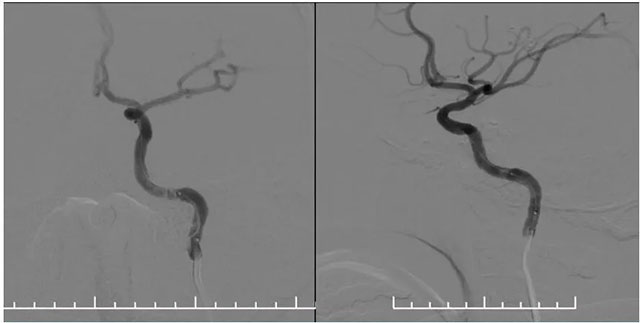

再次超选至左侧锁骨下动脉近椎动脉开口处,单次造影后明确开口狭窄程度,测量狭窄段长度及近远端血管直径,选取合适球囊。随后在微导丝辅助下通过支架内再狭窄段超选至左侧椎动脉V2段,选用2.5*15球囊,沿微导丝到位于狭窄段,球囊扩张至8atm,再次行椎动脉造影,血流有所改善。再次将球囊下移,球囊扩张至14atm,撤除球囊后行即刻造影示血流较前通畅。选择3.5*15药物洗脱球囊,超选至狭窄处,予以6atm,后撤除球囊,行即刻造影示血流较前明显改善,再次行椎动脉造影双侧大脑后动脉及基底动脉血流通畅。

▲ 药物洗脱球囊在微导丝导引下到位于左侧椎动脉支架内,充分扩张药物球囊使其贴壁

▲ 球囊扩张后,支架内狭窄明显改善,支架贴壁良好